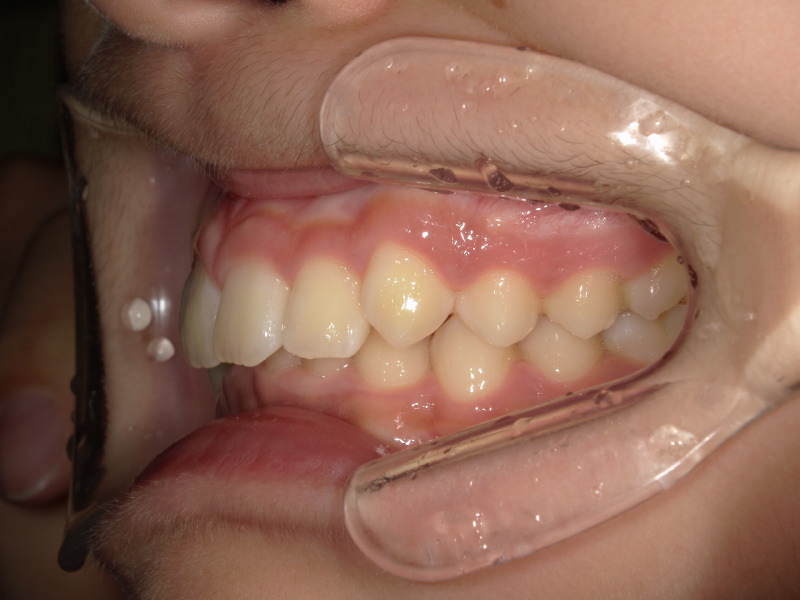

始めの検査の時の写真です。

下の歯があまり見えておらず、横からの写真を見ると上の歯に覆い被さっているように見えます。

過去にこの男の子は他院で上の歯並びのみ矯正をしていました。

確かに上の歯は綺麗ですが、下の歯にはガタつきが残っています。

この時既に歯の生え変わりは終わっており全て永久歯の状態です。